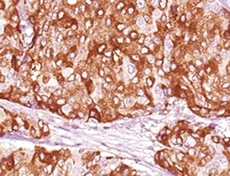

BRCA1 in Human Breast Cancer Tissue. BRCA1 was detected in immersion fixed paraffin-embedded sections of human breast cancer tissue using Human BRCA1 Monoclonal Antibody (Catalog # MAB22101) at 5 µg/mL overnight at 4 °C. Before incubation with the primary antibody tissue was subjected to heat-induced epitope retrieval using Antigen Retrieval Reagent-Basic (CTS013). Tissue was stained using the Anti-Mouse HRP-DAB Cell & Tissue Staining Kit (brown; CTS002) and counterstained with hematoxylin (blue). View our protocol for Chromogenic IHC Staining of Paraffin-embedded Tissue Sections.